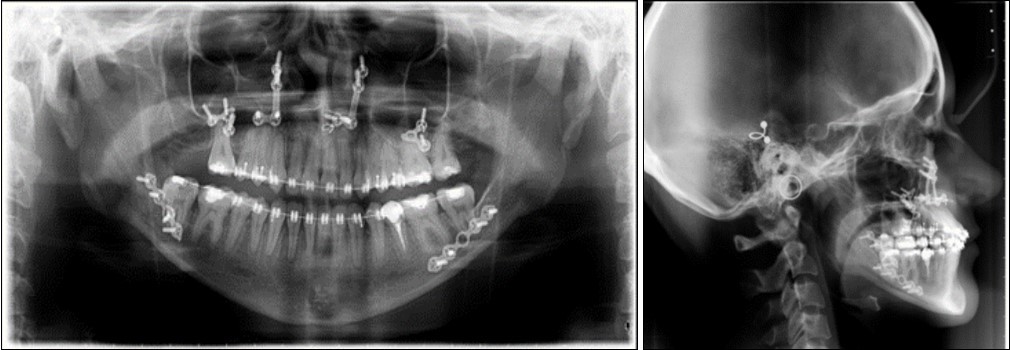

The panoramic radiograph examination showed impacted bilateral mandibular third molars, and one maxillary third molar.Cephalometric analysis disclosed a skeletal class III (ANB -5 degrees), with a retruded maxilla and a protruded mandible (SNA 78 degrees and SNB 83 degrees). The patient is a hyperdivergent type, with FMA 30 degrees and IMPA 77 degrees, which suggests retruded lower incisors. Examination of soft tissue on the profile radiograph shows a concave profile and a protruded lower lip. (Figure 3).

Figure 3.Initial panoramic and lateral cephalometric radiographs

Initial panoramic and  lateral cephalometric radiographs

Post-surgical orthodontic treatment was started 4 weeks after the surgery. Wearing of bilateral box elastics was recommended in order to improve interdigitation. (Figure 6) The orthodontic treatment was finished on 0.019x0.025 SS archwires. Post-surgery cephalometric analysis revealed an increase in SNA value by 4 degrees (SNA 82 degrees) and a decrease in SNB value also by 4 degrees (SNB 79 degrees). The patient was now in a skeletal class I, with ANB 3 degrees. An examination of the soft tissue on the radiograph reveales a better relation between the upper and lower lip. (Figure 7).

Figure 7.Post-surgical panoramic and lateral cephalometric radiograph.

Post-surgical panoramic and lateral cephalometric radiograph.

The use of digital patient records such as x-rays and digital photos, is particularly useful in cases where patients are treated in interdisciplinary teams.19 In the present case report, collaboration between orthodontic and surgical treatment was a success, with excellent esthetic and functional results. From a skeletal class III (ANB –5 degrees), the increase in ANB angle value was 8 degrees after the bimaxillary surgery, final ANB angle value being 3 degrees and a class I skeletal class.